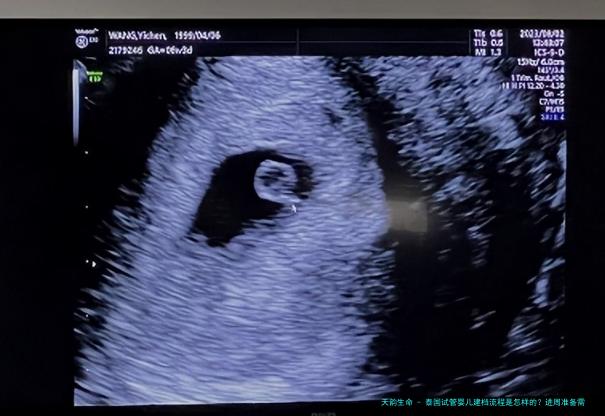

近几载来,跟着试管婴儿技术的不断发展,越发越多的家庭选择去往泰国进行试管婴儿治疗。泰国试管婴儿技术以其成熟、成功率高等优势,吸引了许多的患者。然而,在进行泰国试管婴儿治疗此前,认识建档与进周的相关事项至关重要。本文将为您详细介绍泰国试管婴儿的建档与进周过程,帮助您更好地准备这一路程。